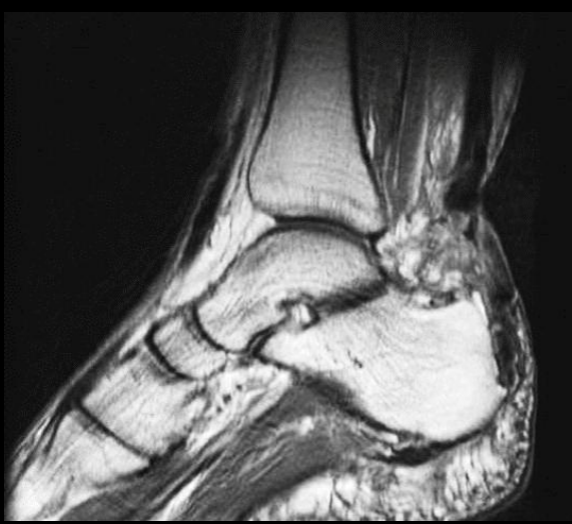

15

A

Rotura tendón de aquiles

Edema Hiperintenso